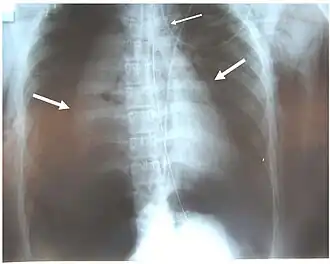

La radiografía de tórax es la técnica de imagen inicial usada para diagnosticar la LCT.[17] La radiografía puede no tener ningún signo en un paciente por lo demás asintomático.[15] Las indicaciones de LCT vistas en las radiografías incluyen deformidad en la tráquea o un defecto en la pared traqueal.[17] La radiografía también puede mostrar enfisema cervical, aire en los tejidos del cuello.[2] Las radiografías también pueden mostrar lesiones y signos acompañantes como fracturas y enfisema subcutáneo.[2] Si se produce un enfisema subcutáneo y el hueso hioides aparece en una radiografía a una altura inusual en la garganta, puede ser un indicio de que la tráquea ha sido seccionada.[4] También se sospecha de LCT si un tubo endotraqueal aparece en una radiografía fuera de lugar, o si su manguito parece estar más lleno de lo normal o sobresale a través de un desgarro en las vías respiratorias.[17] Si se desgarra un bronquio en toda su extensión, el pulmón puede colapsarse hacia fuera, hacia la pared torácica (en lugar de hacia dentro, como suele ocurrir en el neumotórax), porque pierde la unión al bronquio que normalmente lo mantiene hacia el centro.[6] En una persona tumbada boca arriba, el pulmón se colapsa hacia el diafragma y la espalda.[23] Este signo, descrito en 1969, se denomina signo del pulmón caído y es patognomónico de LCT (es decir, es diagnóstico de LCT porque no se produce en otras afecciones); sin embargo, sólo se produce en raras ocasiones.[6] Hasta en uno de cada cinco casos, las personas con traumatismo contuso y LCT no presentan signos de la lesión en la radiografía de tórax.[23] La TC detecta más del 90% de los TLC resultantes de traumatismo contuso,[3] pero ni la radiografía ni la TC sustituyen a la broncoscopia.[6]